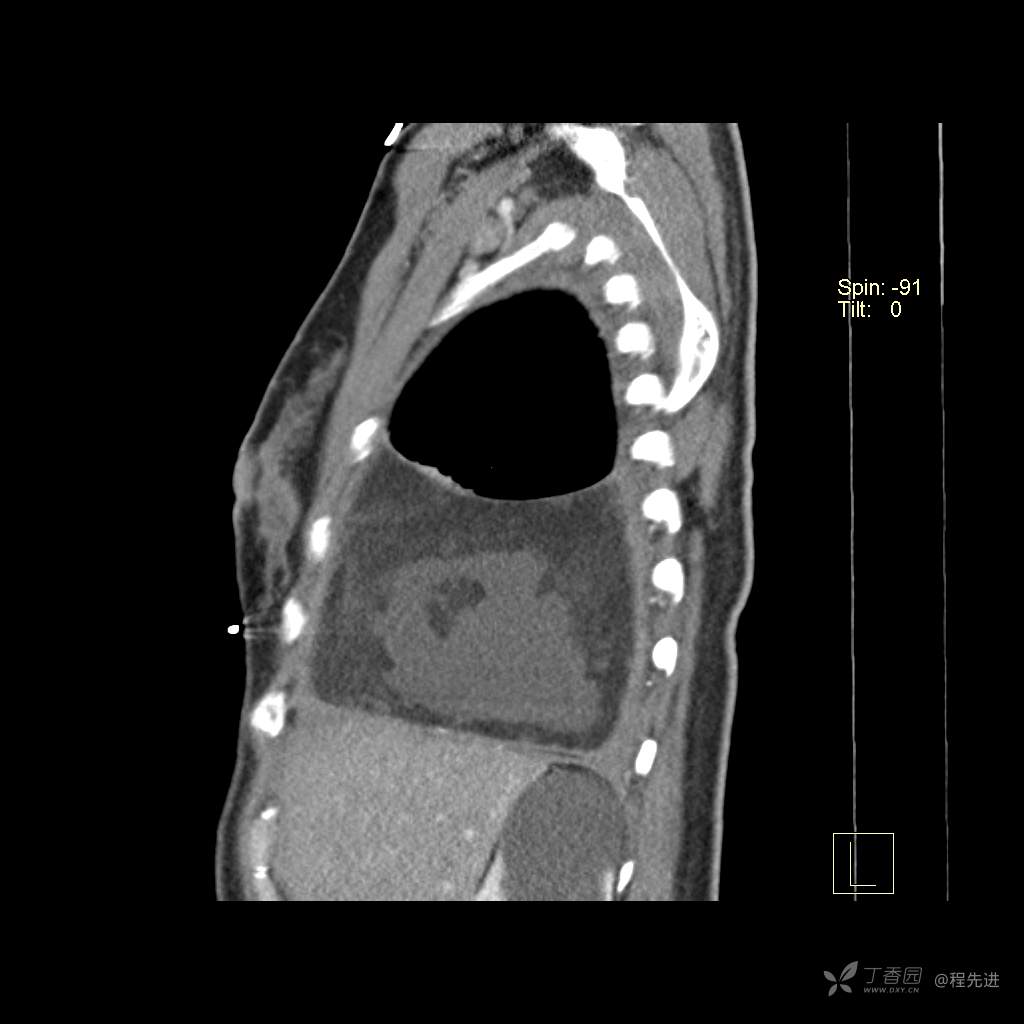

患者性别:女

患者年龄:51岁

简要病史:胸闷半年

肺淋巴管肌瘤病 (7)

乳糜胸 (8)